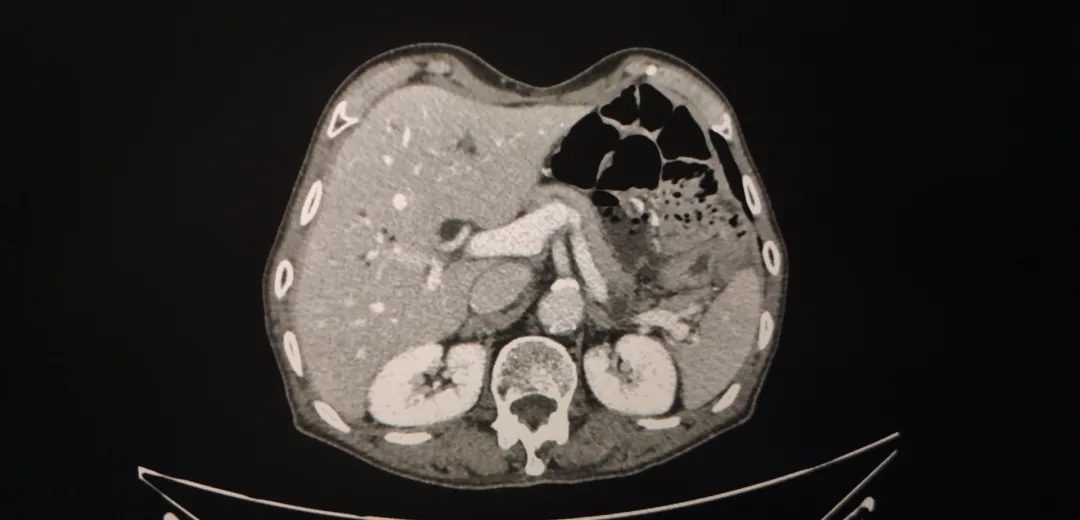

腹盆腔强化CT(2018-4-4):1、胃体及胃窦胃壁增厚,考虑胃癌;2、胃周、胃左动脉区及腹膜后多发肿大淋巴结,考虑转移;3、肝内胆管结石,肝内胆管轻度扩张;4、左肾囊肿,左肾上腺增厚,考虑增生;5、前列腺增生伴钙化;6、盆腔少量积液;7、两下肺实变索条,左侧胸腔少量积液。

图1-1 2018-4-4 箭头为胃周肿大淋巴结